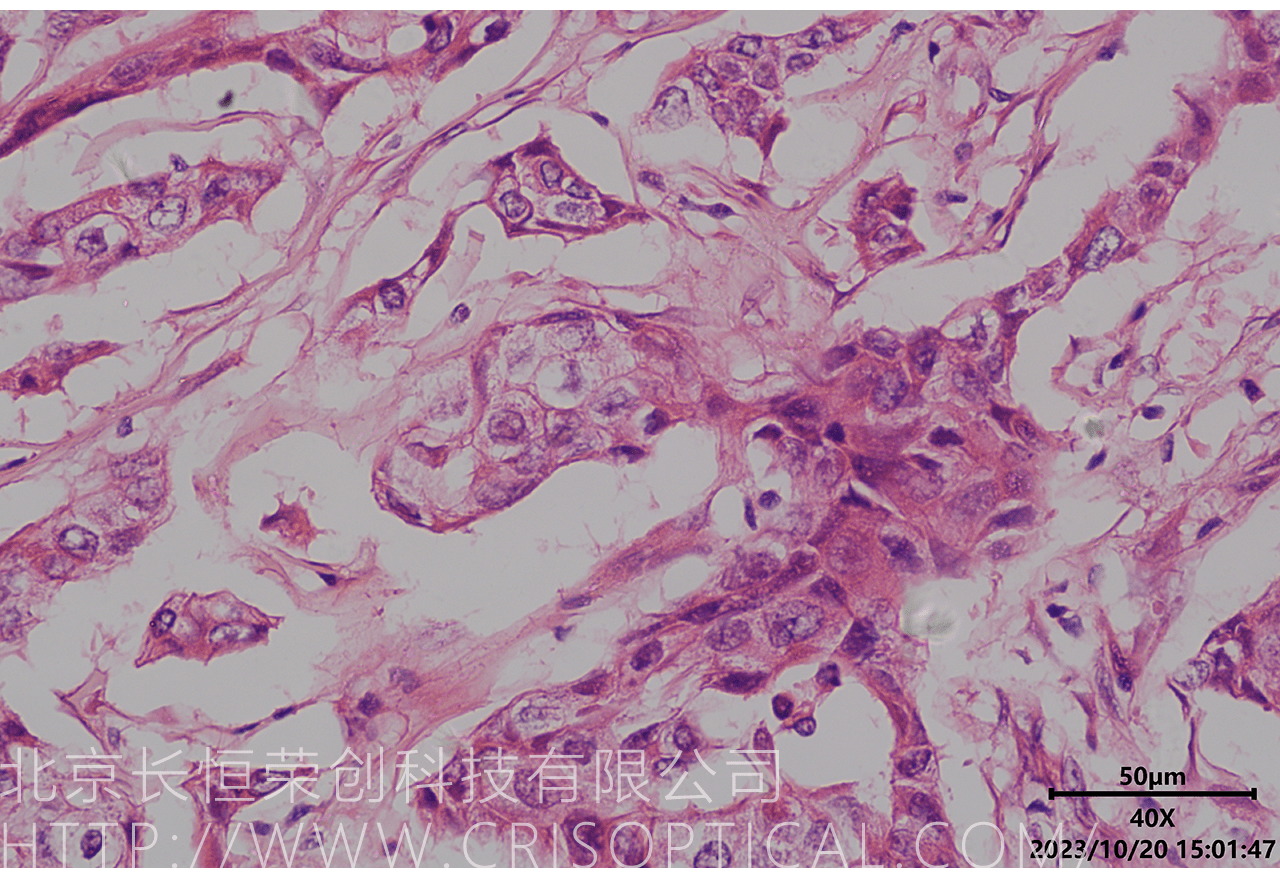

病理切片觀察是一種重要的醫學實踐,通過對組織和細胞切片的

顯微鏡觀察,幫助醫生診斷疾病、評估病情和制定治療方案。病理切片觀察在

臨床醫學、癌癥診斷、外科手術和疾病研究中發揮著關鍵作用。

腫瘤診斷:對癌癥和其他腫瘤的病理切片觀察是確定腫瘤類型、分級和分期的關鍵步驟。醫生通過觀察組織樣本中的細胞形態、核形狀、分裂活性和其他特征,可以識別腫瘤的類型,幫助決定治療方法。